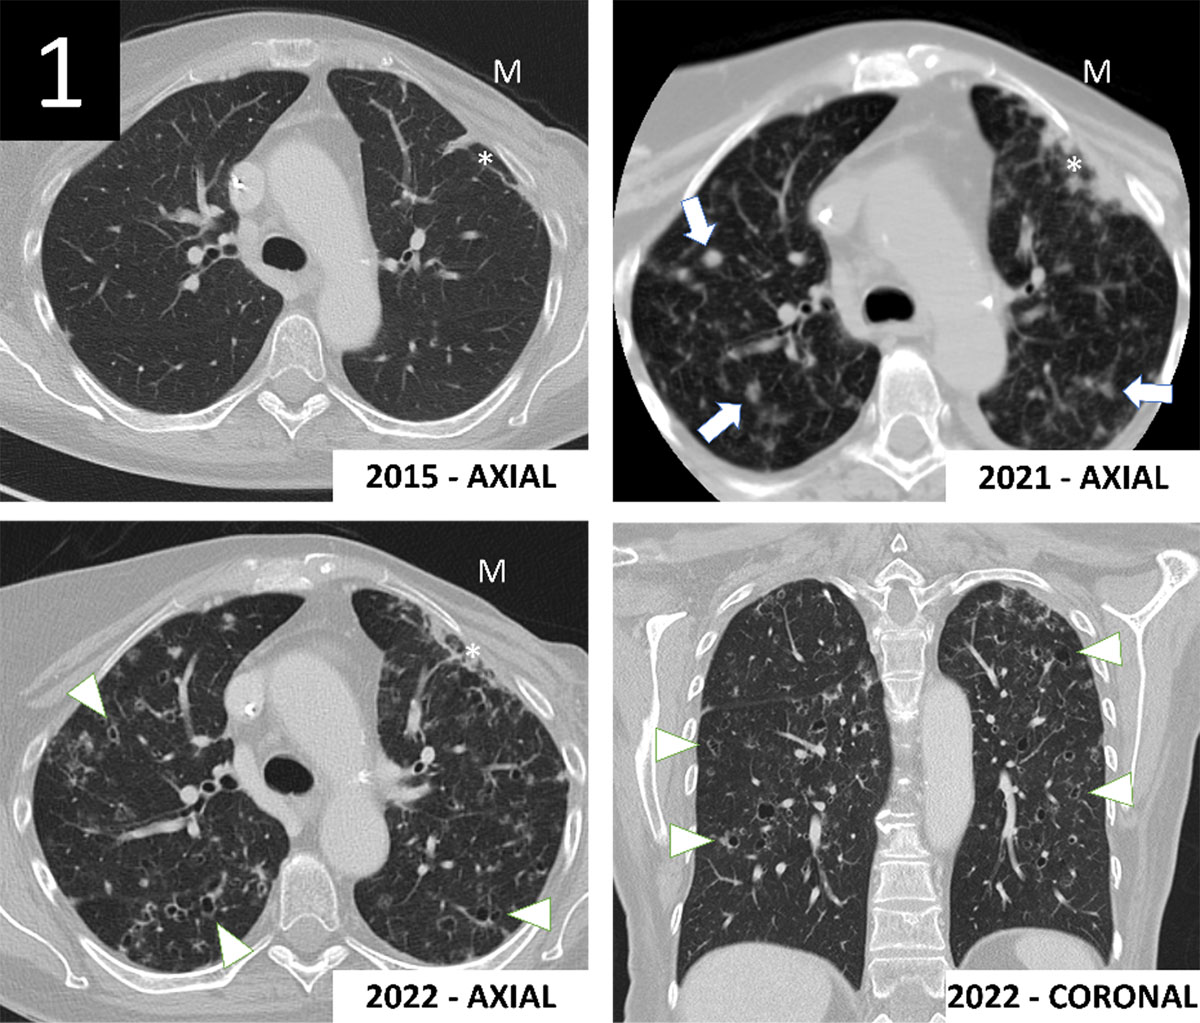

A 65-year-old woman was in follow up for a curatively treated breast cancer in 2014. Medical history mentioned heavy smoking behavior of 35 pack years (Figure 1). A surveillance CT scan in 2015 showed left-sided status after mastectomy (M) with focal pulmonary radiofibrosis (*) and no focal pulmonary lesion. A CT scan in 2021 showed disseminated centrilobular nodules (white arrows). A follow-up CT in 2022 revealed cystic transformation of these previously solid lesions (arrowheads). The coronal plane shows the distribution of these cysts in the upper and middle parts of the lungs, sparing the costophrenic angles. At this time, the patient had elevated tumor marker CA 15–3 and inflammatory markers, without physical complaints. Clinically and radiologically, the differential diagnosis consisted of cystic lung metastases versus pulmonary Langerhans cell histiocytosis (PLCH).

Figure 1